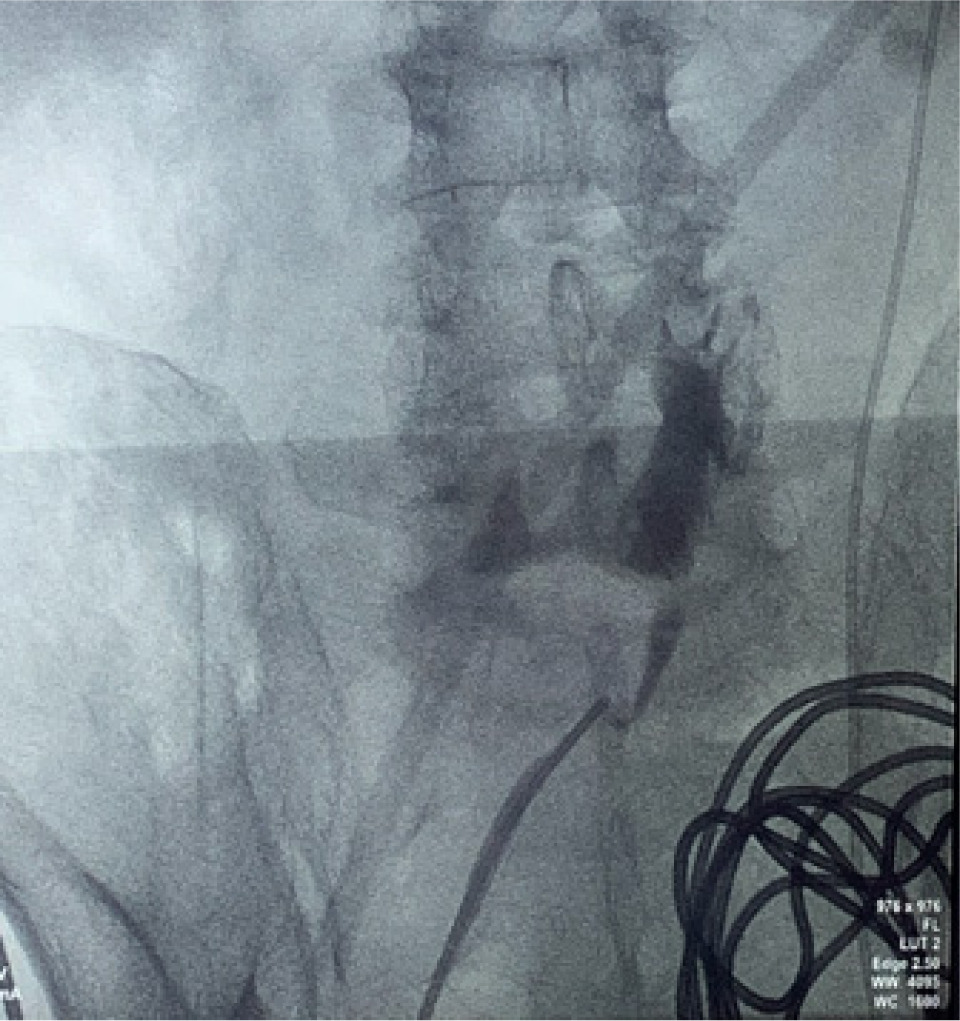

A 74-year-old Chinese male patient, ex-smoker, and social drinker, with a history of carcinoma of prostate in remission with laparoscopic radical prostatectomy done 11 years ago presented with an incidental finding of a right abdominal mass without frank symptoms. Preoperative eGFR ranges from 80 to 90 mL/min/1.73m2. Computed tomography (CT) showed a 7 cm heterogeneous mass on the right side of the HSK with complex hilar anatomy (Figures 1 & 2). Dual tracer (C-11 acetate and F18 FDG) positron emission tomography (PET-CT) showed moderate and mildly avid renal cell carcinoma (RCC) arising from HSK, without nodal or distant metastases. A 3D image reconstruction using FUJIFILM Synapse system was performed, showing complex tumor and vascular anatomy (two renal arteries and an additional artery to isthmus) (Figure 3). An open partial right nephrectomy was planned.

Figure 1: Axial cut of arterial phase-enhanced CT abdomen at the tumor level.

Figure 2: Axial cut of delayed phase-enhanced CT abdomen at the tumor level.